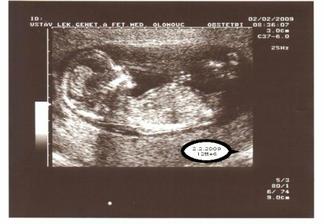

18.12.2008 první kontrola u lékaře.Vše v pořádku,na UTZ už bylo vidět srdíčko...Je 23.12.2008 a cítím,že přibírám.Vůbec nezvracím,jen je mi občas na omdlení a hodně spím...2.1.2009 Stále jsem hodně spavá a unavená.Občas je mi trochu špatně,ale nezvracím.Chutě mám různé,ale co opravdu vede-jsou polévky.Ty zbožňuju 🙂 Přibírám,ale zatím nejde poznat,že jsem těhotná...9.1.kontrola,miminko je 2,6 cm velké,fotka z ultrazvuku se doktorovi moc nepovedla,ale na monitoru už to začínalo vypadat jako človíček 🙂Dostala jsem těhotenskou průkazku,dle UTZ jsem 9+3,termín porodu 11.8.2009.Sestřička mi pak brala krev,měřila tlak-ten mám bohužel hraniční (140/85).Stále bývám unavená,často mě opravdu hodně bolí nohy,ale jinak je mi dobře...14.1.Mám za sebou EKG...2.2.jsme byli v Olomouci na genetice.Miminko bylo na UTZ moc nádherné.Krásně mu tlouklo srdíčko.Brali mi také krev.Zatím to vypadá,že se vše vyvíjí tak,jak má.Jsem moc šťastná.Poprvé byl se mnou na UTZ i přítel,bylo to úžasné...Kontrola u obvodní lékařky mě uklidnila.Vysoký tlak nemám.Přesněji,jsem z měření nervozní a tím se zkreslují výsledky...Po nemoci jsem něco zhubla,takže v 15.týdnu jsem zatím 2kg v plusu.Hodně mi porostly prsa.To je daleko znatelnější než bříško-zatím 🙂 ...13.2.jsem byla v poradně.Doktor už měl výsledky z genetiky,které dopadly výborně.Další kontrolu mám za měsíc...Tento týden jsem začala číst miminku.Vybrala jsem si Kroniku města Kocourkova.Bavím se tím i já.Každý večer jednu kapitolku.Doufám,že miminko cítí,že se na něj moc těšíme....20.2. jsem ucítila první pohyby.Překvapilo mě to moc.Byla jsem teprve v 15tt+3.A čekám první mimi.Bylo to velmi jemné,jako by mi tam proplula rybička,takové zašimrání...Hrozně zvláštní.Ležela jsem a měla přitisklou dlaň na bříšku a najednou-jakoby se mi něco vevnitř otřelo o stěnu.Zatím to jinak výrazně necítím.Už vůbec ne během činnosti a není to žádné kopnutí....13.3.jsem byla na další kontrole.Miminko uvidíme na velkém ultrazvuku 24.3.Jsme moc napjatí,protože si chceme nechat říct pohlaví....Taky jsem stihla kontrolu u zubařky.Naštěstí vše v pohodě-jako před těhu 🙂 ...21.3. přes pupík mám 97 cm 🙂...24.3.byli jsme s přítelem na velkém ultrazvuku.Miminko má 20 cm a váží 350 g.Vrtělo hlavičkou a dokonce si i zívlo 🙂Doktor všechno možné poměřil,zkontroloval,ukázal.Dokonce si tipl pohlaví mimouška.Ale víme to jen my s přítelem a tak to zůstane až do porodu-překvapení pro ostatní 🙂 Máme 15 min. záznam na DVD...30.3. podrobné interní vyšetření-zjištěn možný syndrom bílého pláště 🙂....